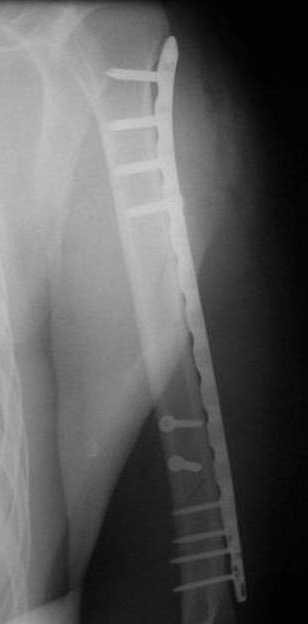

ранение той же пулей). Выполнен минимально инвазивный остеосинтез

блокируемой метадиафизарной пластиной, повторная хирургическая

обработка ран плеча. Заживление всех ран первичное, сращение

наступило в обычные сроки.